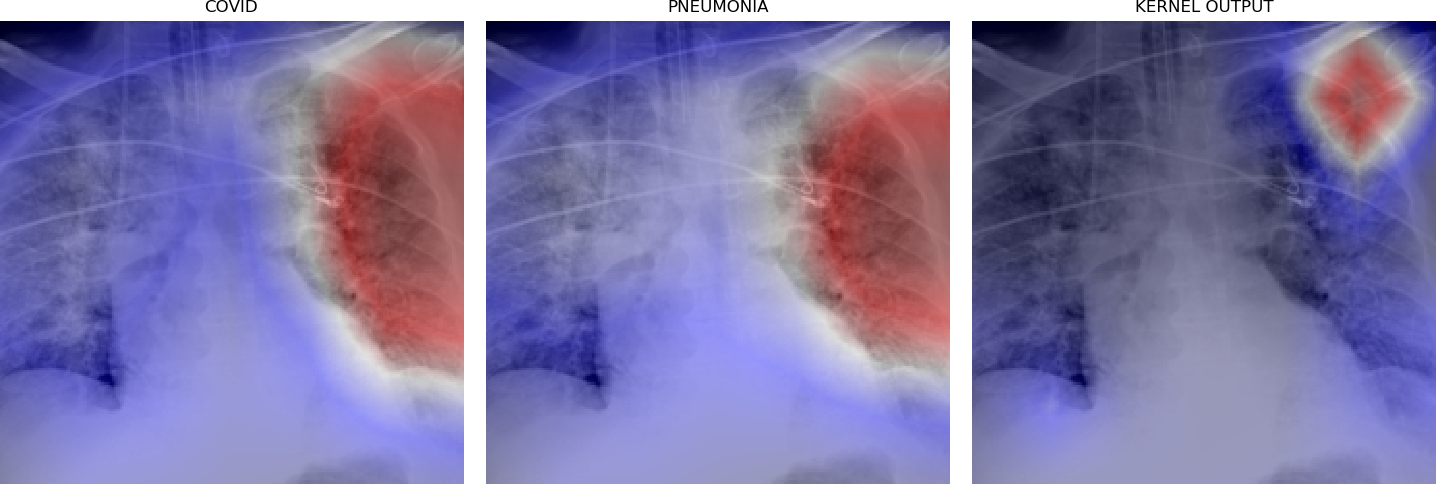

Figure 5 shows triples of X-ray images with superimposed class activation maps for predictions obtained from expert binary models (images one and two) with the third image showing the heat maps computed using our kernel. The intended use of our method is to examine positive classifications from two possibly overlapping classes (i.e. COVID-19, Pneumonia) and extract discriminative features pertaining to the class of interest, i.e. COVID-19. Triples (a)-(f) show positive classifications of COVID-19 and Pneumonia by their respective binary expert models along with class activation maps that localize the image region responsible for that classification. The third image in each triple shows a better localized image region for COVID-19 as computed using our method. Our method is intended to improve explainability of predictions under circumstances where both models return positive classifications resulting in significant overlap in activation maps.

Figure 6 demonstrates the role of the kernel parameter . It controls amplification of the directed differences among the activation maps. Higher values of concentrate the resulting heat map to a smaller region.